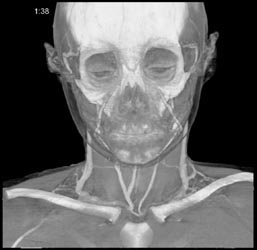

Av Shunt in Liver